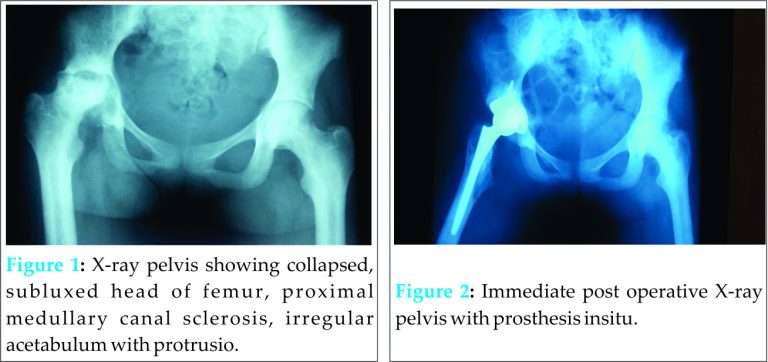

A 28-year-old female nursing student who is a Jehovah’s Witness from Akwa Ibom state, Nigeria presented with a three year history of pain in the right hip which had been progressively worsening with noticeable shortening within one year duration. Pain was worse while walking and restricted home chores and school activities. She is a known SCD patient diagnosed in childhood who had never attended a sickle cell clinic and did not know her steady state haemoglobin. Her last crisis which was that of bone pains was ten years prior to admission. Examination showed an underweight patient with body mass index of 17.9kg/m2, with an anthalgic gait mobilizing using a walking stick. She had a tender right hip with hip flexion of 50 degrees, abduction and adduction of 10 degrees with zero internal rotation, external rotation and extension due to pain. Her Harris hip score was 53 and she had a limb length discrepancy of 2 cm. Her heamoglobin was 10g/dl, ESR 45mm/Ist hr, WBC 16000/mm3, neutrophils of 72%, lymphocytes of 28%. The liver function test, serum electrolytes, urea and creatinine, fasting blood sugar, urinalysis, were all within normal ranges. X-ray of the hip is as shown in (Fig. 1).

A diagnosis was made of avascular necrosis of the head of femur in a SCD and Jehovah’s Witness patient who will not accept blood in any form and had a durable power of attorney to the effect. She was thoroughly counseled and started on erythropoietin injections 4000 units three times a week prior to surgery. The anaesthetist decided on a blood conservation technique by way of acute hypervolemic hemodilution in theatre with general anaesthesia in order to achieve a close control of desired blood pressure using hypotensive anaesthesia. The blood pressure ranged between 85/50mmHg and 100/60 mmHg from a baseline of 120/80mmHg. Measures to avoid hypothermia, hypoxia, and detrimental hypotension were instituted to avoid complications of sickling. The lead surgeon was the most experienced and fastest surgeon. Diathermy and bone wax were used during surgery. Perioperative nurses and health attendants were also prepared to avoid undue delays in providing required materials and instruments. The radiographer was at hand to operate the image intensifier for locating the medullary canal. The duration of surgery was 4 hours 32 minutes with an estimated blood loss of 1200mls and urine output of 1600mls. Difficulty was encountered locating the medullary canal as following the neck cut, complete absence of cancellous bone was noted with only sclerotic bone seen and patient had femoral perforation. A size 6 stem was all the created canal could take and acetabulum received a size 48 cementless cup and neutral liner, the head size was 28+1.5. Bone graft from the head of femur was packed into acetabulum for the protrusio and two screws used for added stability to the shell. Post operative haemoglobin was 7.7 g/dl, ESR 35mm/Ist hr, WBC of 16600/mm3, neutrophil of 66%, lymphocyte of 34% and the patient did not have any crises post operatively. She was placed on extended antibiotic prophylaxis for 10 days, commenced on antithrombotic day one post operative, pain control and haematinics. Her post operative X-rays were satisfactory (Fig. 2). She was allowed to sit up on post operative day one and mobilized on partial weight bearing on third day post operatively. She has had three months of follow up and is doing well with a Harris hip score of 89 at six weeks.